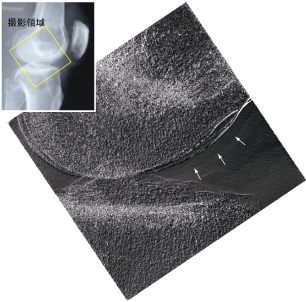

図4は献体の膝部分を本装置で撮影した画像です。微分位相画像では、矢印で示すように軟骨の輪郭が描出されていますが、従来のX線撮影では見えません。リウマチを患うと、まずこの軟骨組織に変化が現れるので、本装置がリウマチの早期診断に有用であると期待されます。

図4 ヒト(献体)の膝の撮影結果(微分位相像)

埼玉医科大学に設置した装置で撮影した画像です。矢印で示すように、骨の輪郭に沿ってもう1本の輪郭が描出されています。これは、その形態や厚みから関節軟骨の輪郭に合致すると考えられます。従来のX線写真(左上)では描出が困難であった構造です。